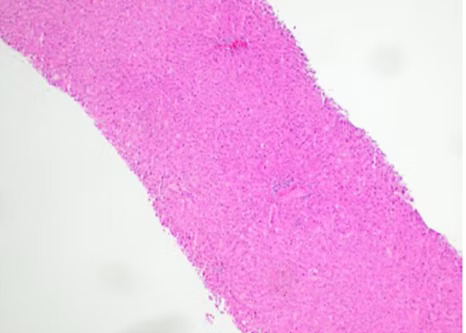

RESTARI's MorCor® full core biopsy device takes excellent biopsy specimens without the fragmentation of side notch devices.

"Linear samples exhibited no crush artifact or cellular distortion".

"Overall the specimens were 90% better than similarly acquired tissues." A prominent pathologist's summary.